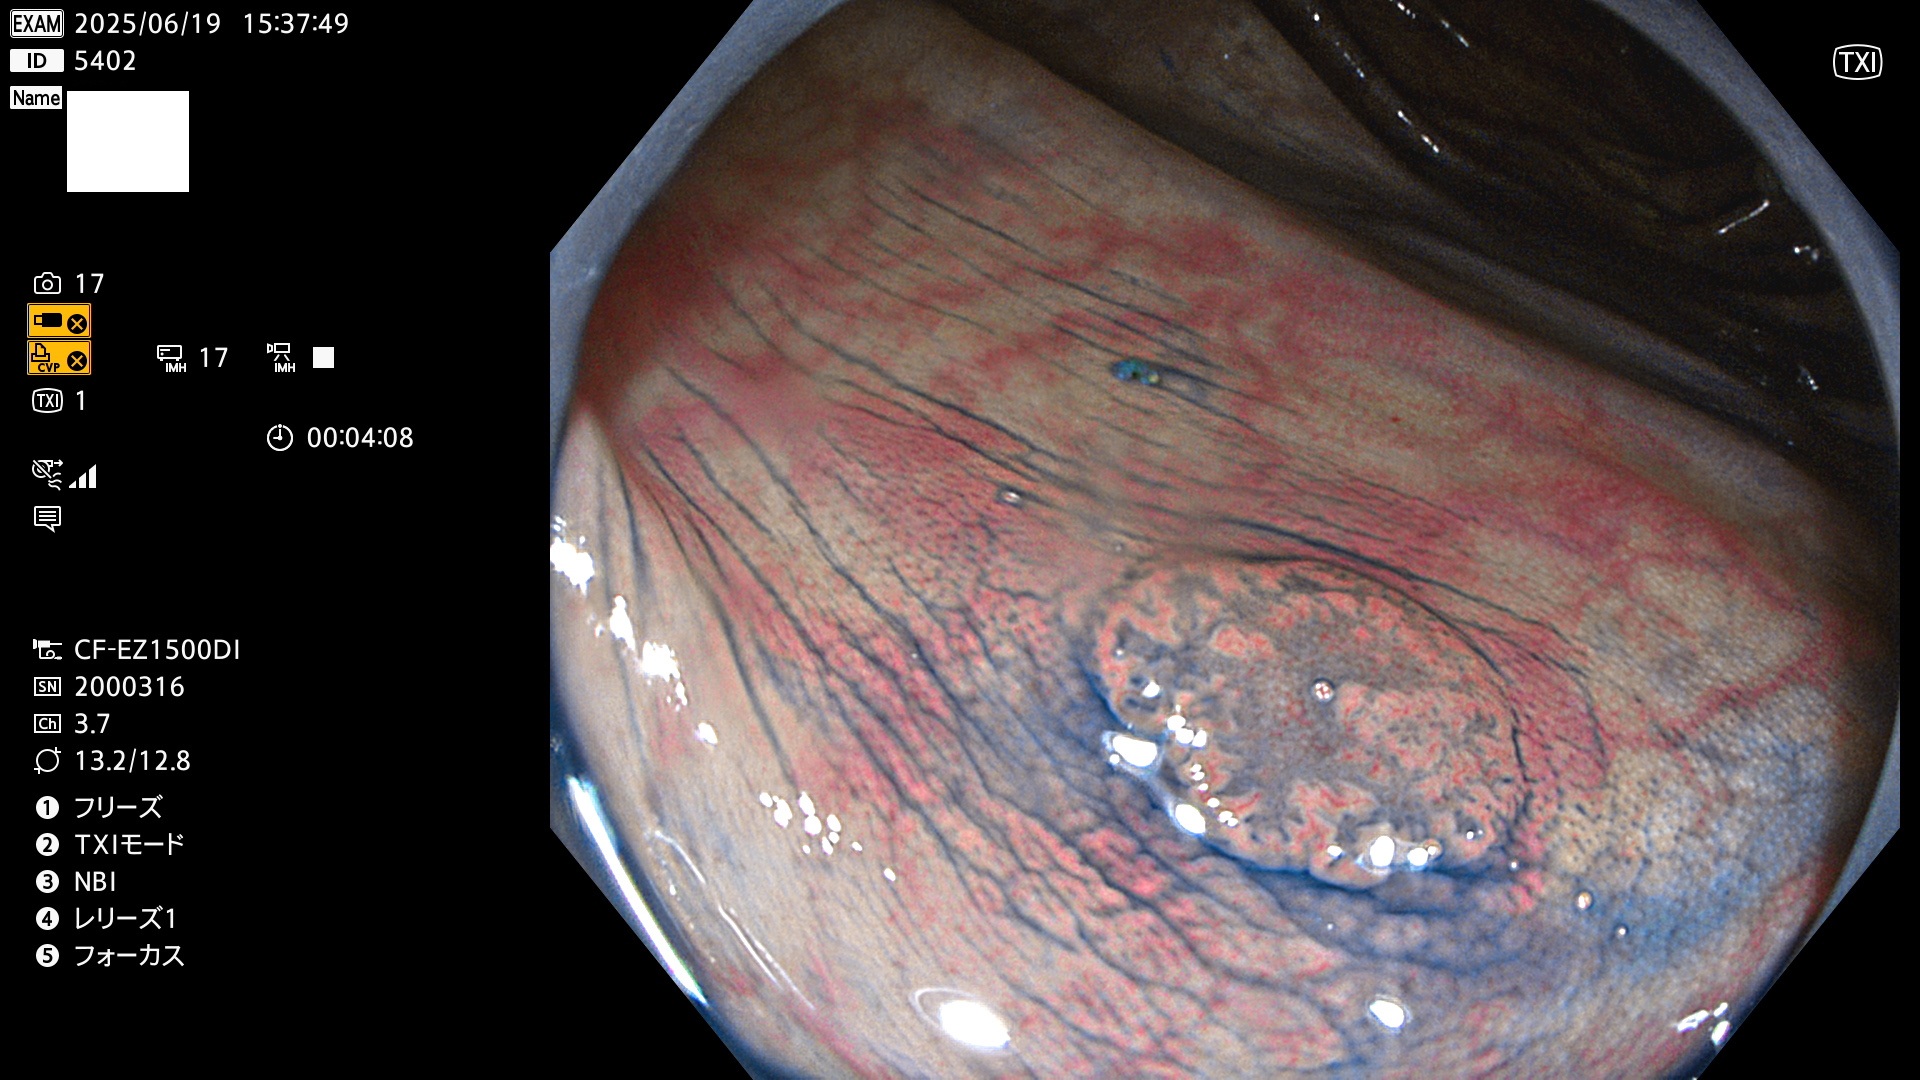

今週のUb、Uc型腺腫

完全に平坦な物をUb、陥凹している物をUcと呼びます。Ubは認識が困難で、Ucはびらん(炎症)と紛らわしいために見落とされやすく、「内視鏡後・大腸癌」の原因になります。

抽出の対象期間 2025年6月19日〜6月22日の4日間(48件の検査)10個 (10/48=20%)